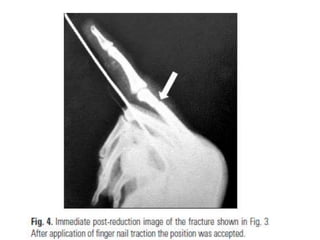

• Prospective study- 43 fractures • Inclusion criteria – Functionally unstable fractures – Unacceptable radiographic alignment (>10° in both AP and lat)

• RESULTS. – Goodfunction - 35 patient – Fair – 6 – Poor – 2 (TAM less than 180) • Nail traction with digital splint is an effective and safe technique

Acceptable Reduction- criteria 1.<10º axial angulation – AP 2. <15º axial angulation - lateral view 3. No rotation 4. No collapse